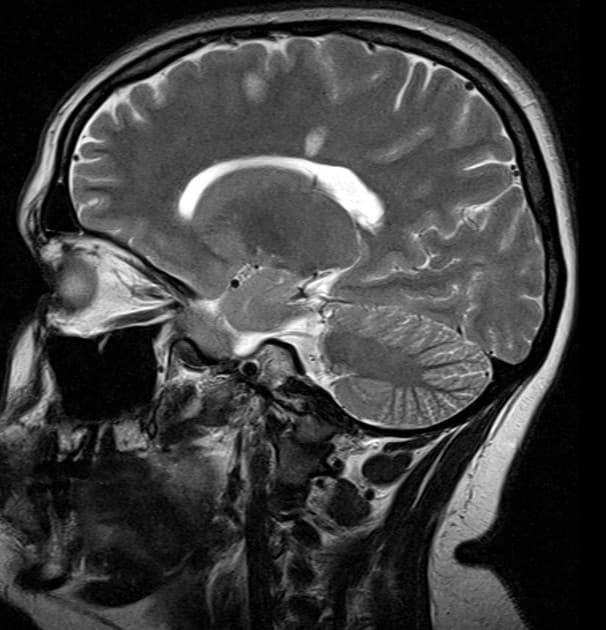

Bệnh nhân 9 ngày sau khi cố tự tử bằng cách thắt cổ, có ngừng tim ngoài bệnh viện. Lâm sàng ghi nhận bệnh nhân trong tình trạng hôn mê, không có phản xạ thức tỉnh, không có phản xạ thân não, ngoại trừ duy trì hoạt động hô hấp, kèm theo các cơn co giật lặp đi lặp lại.

- Hạn chế khuếch tán (restricted diffusion) lan tỏa ở chất trắng vùng trên lều tiểu não, tương ứng với các vùng tăng tín hiệu trên hình ảnh FLAIR.

- Ngoài ra, có các vùng tăng tín hiệu trên FLAIR ở dải vỏ não (cortical ribbon) và các nhân nền (basal ganglia) hai bên, với hạn chế khuếch tán tương ứng nhẹ ở vùng vỏ quanh vận động (peri-rolandic cortex).

Xét theo tiền sử bệnh lý, các phát hiện hình ảnh này phù hợp với bệnh lý thoái hóa trắng sau thiếu oxy chậm (delayed posthypoxic leukoencephalopathy) sau tổn thương não do thiếu oxy-thiếu máu (hypoxic-ischemic encephalopathy).

- "Chụp cộng hưởng từ cho thấy hạn chế khuếch tán lan tỏa ở chất trắng và tăng tín hiệu trên FLAIR, thường kèm theo tổn thương ở vỏ não và nhân nền."